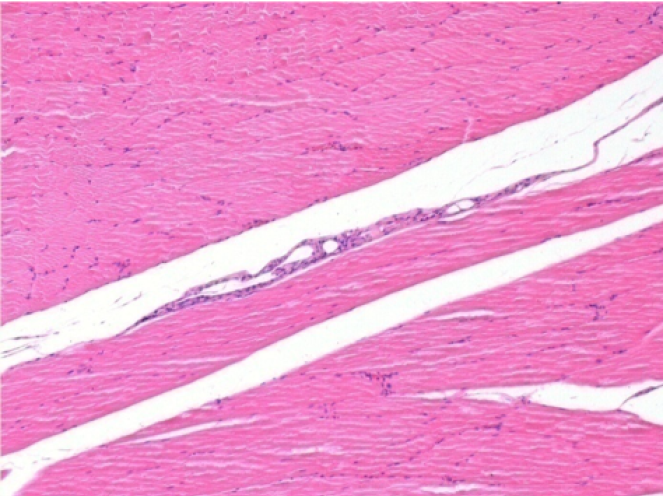

10 días después de la inyección de Endopeel 0,1 ml en el músculo pretibial derecho.

Aquí puede ver la formación de las vacuolas que están rodeadas de linfocitos. Las vacuolas son diferentes a la necrosis tisular. La presencia de linfocitos está relacionada con la permeabilidad de las membranas celulares.

07